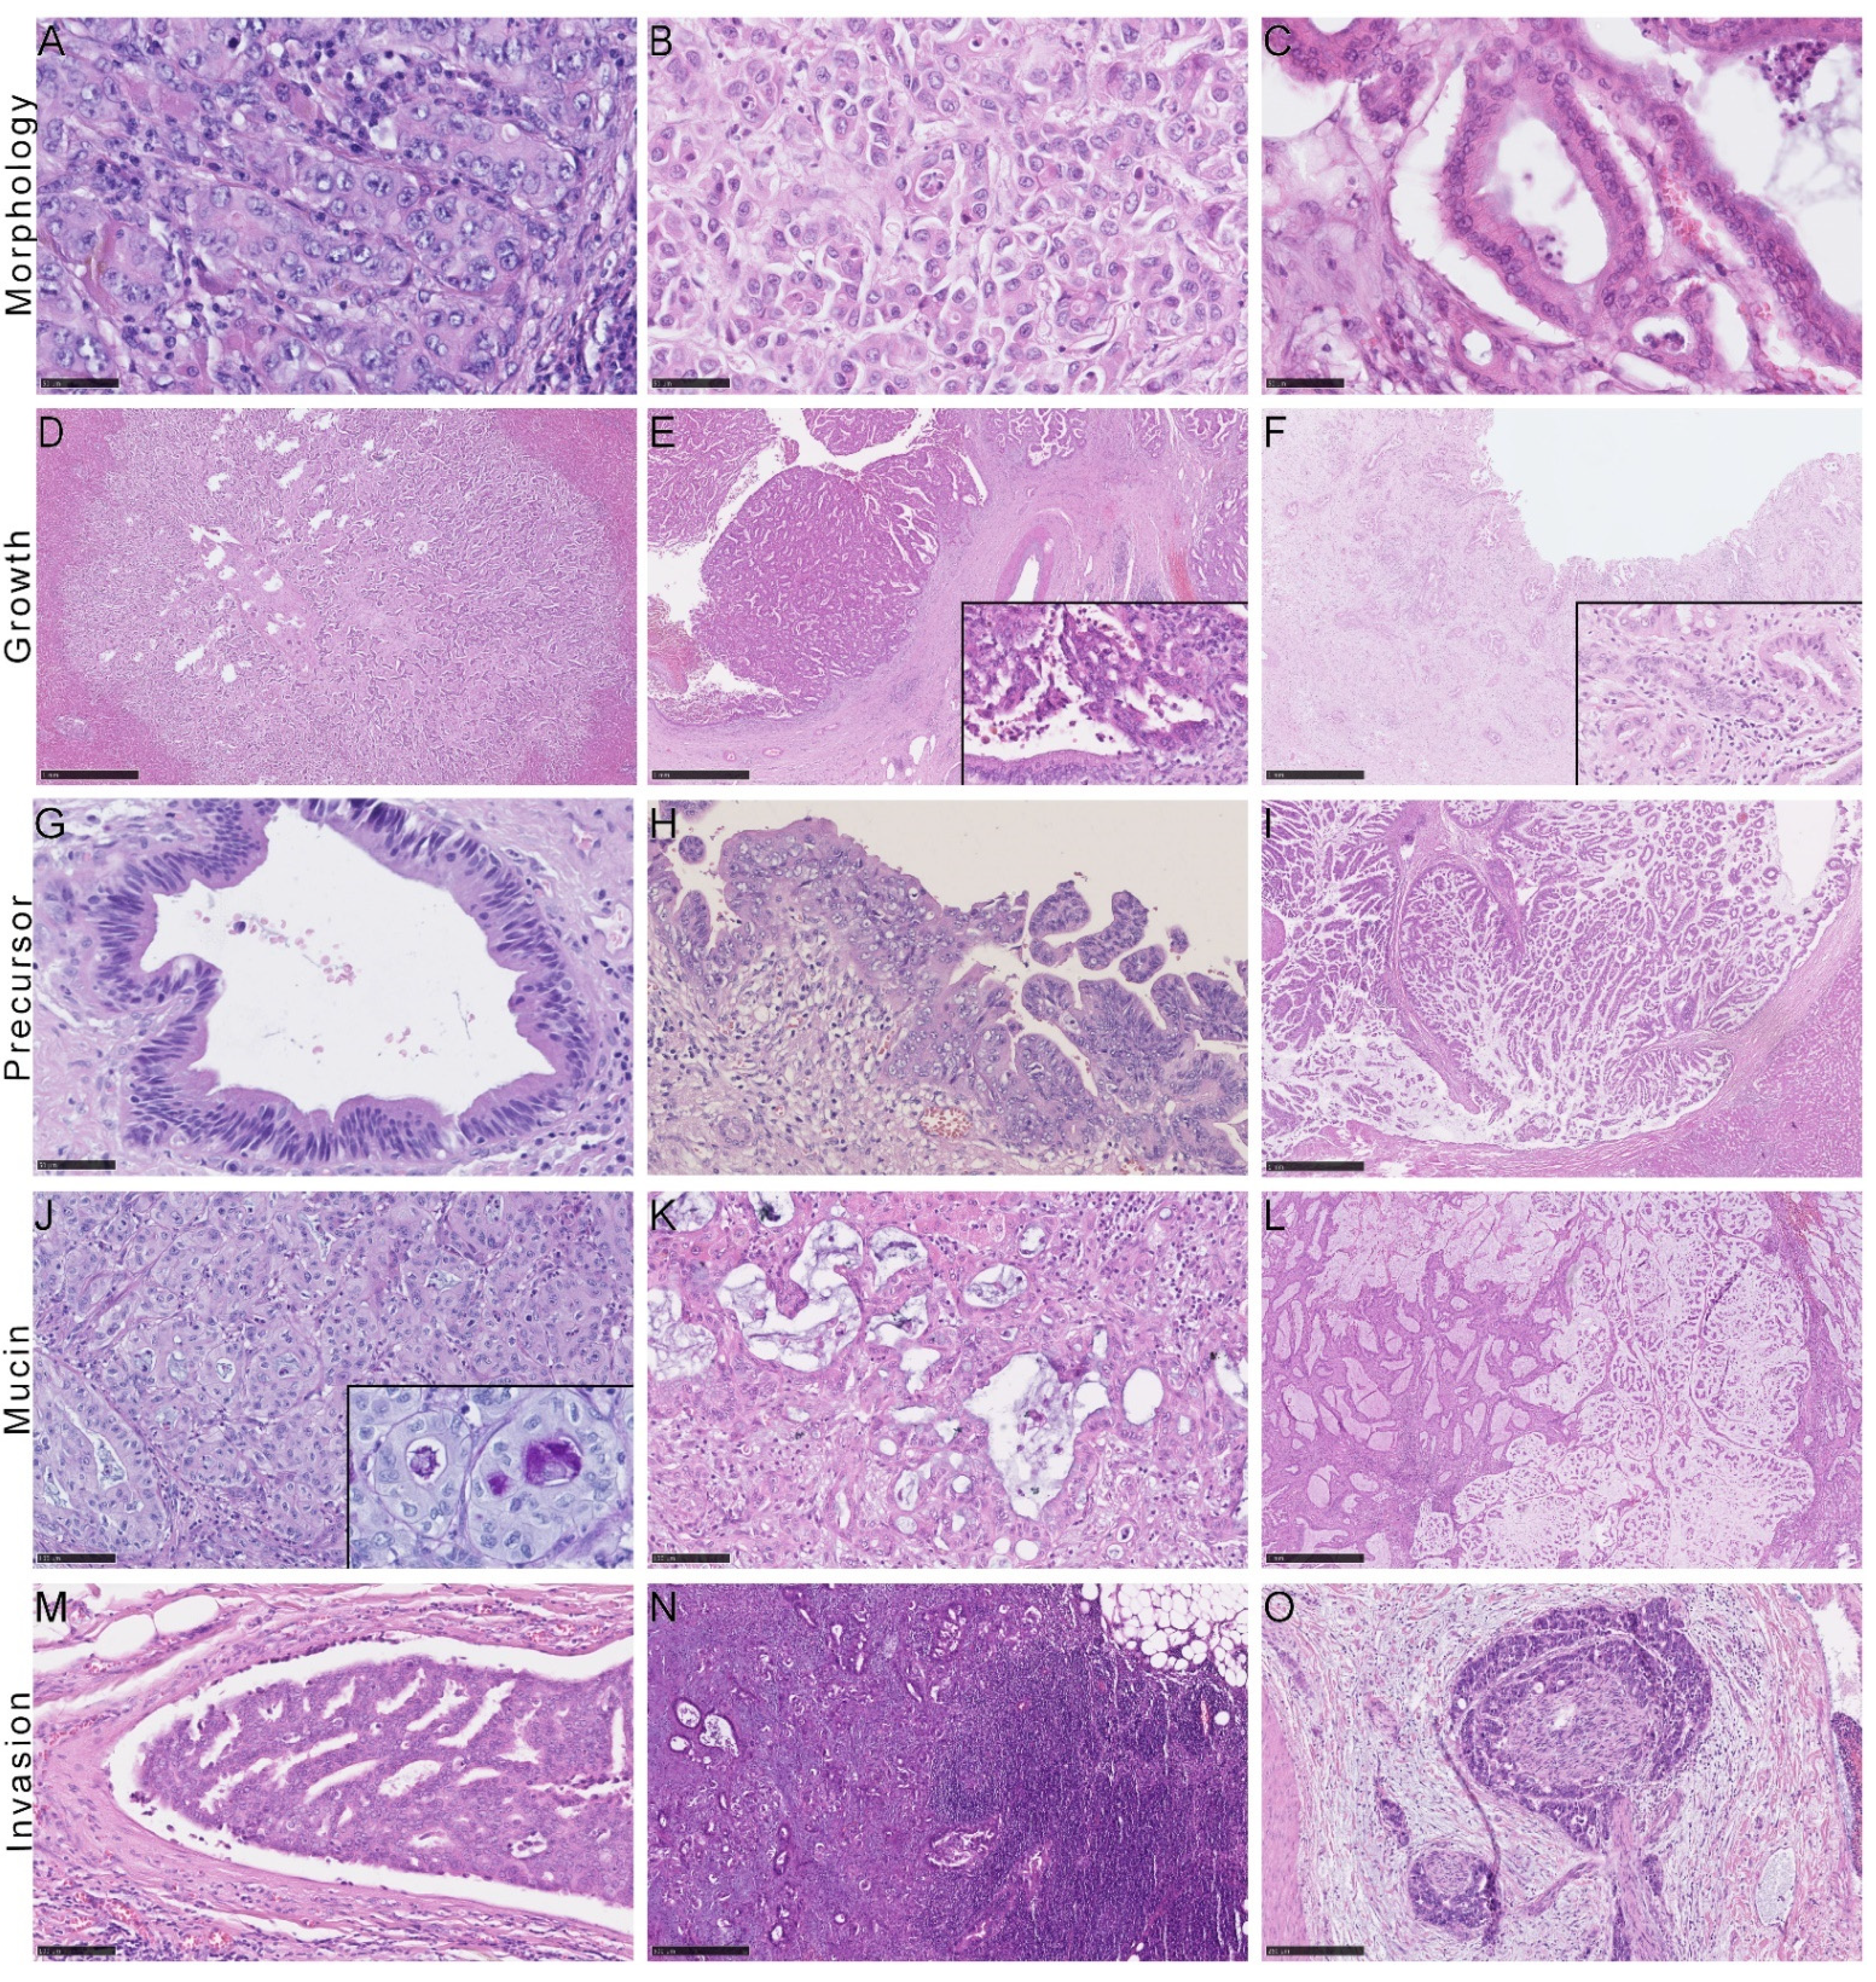

2.3. Histological and Immunohistochemical Features of iCCA Subtypes

| BilIn/IPNB [%] | 0/0 | 64/ 11 | <0.001 | 0.731 | <0.001 | 91.69 | 5.71–1472.03 | |

| BilIn low/high-grade [%] | 25/ 75 | |||||||

| Mass-forming [%] | 99 | 78 | <0.001 | 0.342 | ||||

| Intraductal-growing [%] | 15 | 12 | 0.156 | |||||

| Periductal-infiltrating [%] | 3 | 57 | <0.001 | 0.605 | ||||

| Mucin [%] | 88/10/2/0 | 18/56/24/2 | <0.001 | 0.696 | <0.001 | 13.70 | 4.31–43.55 | |

| Necrosis [%] | 36/27/29/8 | 25/32/37/6 | 0.131 | 0.599 | 1.22 | 0.57–2.58 | ||

| Desmoplasia [%] | 36/55/9 | 14/67/19 | <0.001 | 0.282 | 0.011 | 4.41 | 1.37–14.23 | |

| Pn1 [%] | 16 | 40 | <0.001 | 0.293 | 0.666 | 1.36 | 0.33–5.63 | |

| IHC | CK7 [%] | 1/8/91 | 1/4/95 | 0.369 | 0.149 | 2.94 | 0.66–13.10 | |

| CK20 [%] | 77/22/1 | 50/41/9 | <0.001 | 0.218 | 0.020 | 2.30 | 1.12–4.72 | |

| Ca19-9 [%] | 12/53/35 | 4/46/50 | 0.027 | 0.177 | 0.186 | 1.54 | 0.80–2.95 | |

| EMA [%] | 4/39/56 | 0/25/75 | 0.008 | 0.204 | 0.055 | 2.13 | 0.97–4.69 | |

| S100 [%] | 72/26/2 | 76/24/0 | 0.498 | 0.792 | 1.23 | 0.25–5.96 | ||

| CD56 [%] | 39/45/16 | 61/33/6 | 0.003 | 0.226 | 0.008 | 0.45 | 0.25–0.82 | |

| N-cadherin [%] | 13/31/56 | 27/33/30 | 0.004 | 0.262 | 0.124 | 0.67 | 0.40–1.13 | |

| CRP [%] | 7/16/77 | 24/26/50 | <0.001 | 0.290 | 0.101 | 0.63 | 0.36–1.11 | |